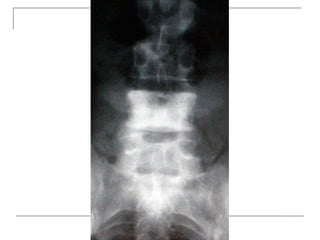

Plain radiograph

 AP

-loss of lumbar lordosis

-reduced disc space

-osteophytes

-deformity

-fracture (increase interpedicular distance)

-osteoporosis

-pedicle disruption

 Lateral

-fracture/wedging

-kyphosis

-spondylolisthesis

 Oblique

-spondylolysis (SCOTTIE DOG)

Plain x-rays